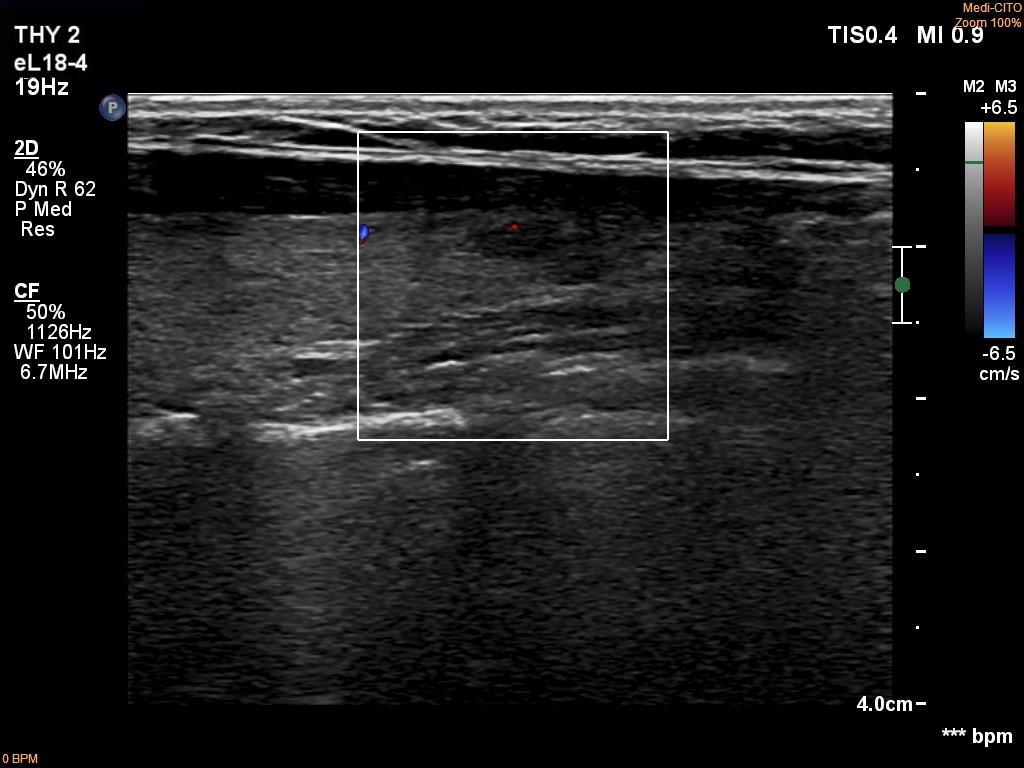

Left lobe, longitudinal scan, color Doppler mode. The lesion is almost avascular.